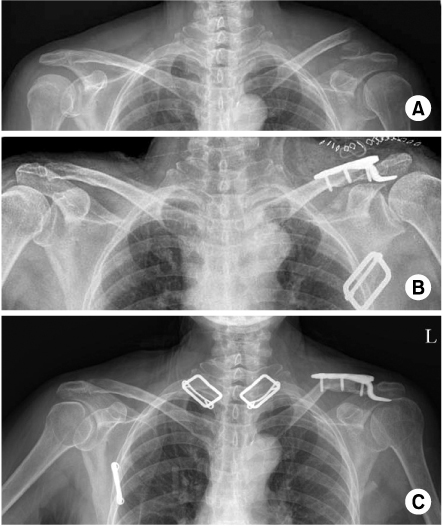

Fig. 3

(A) Preoperative radiograph of the left shoulder of a 49 year old male shows distal clavicle fracture.

(B) This is postoperative radiograph with Hook plate fixation.

(C) At 4 months follow-up, postoperative radiograph shows osteolysis of acromion by the hook of plate.

jkfs-24-48-g003.jpg

Fig. 3 (A) Preoperative radiograph of the left shoulder of a 49 year old male shows distal clavicle fracture. (B) This is postoperative radiograph with Hook plate fixation. (C) At 4 months follow-up, postoperative radiograph shows osteolysis of acromion by the hook of plate.